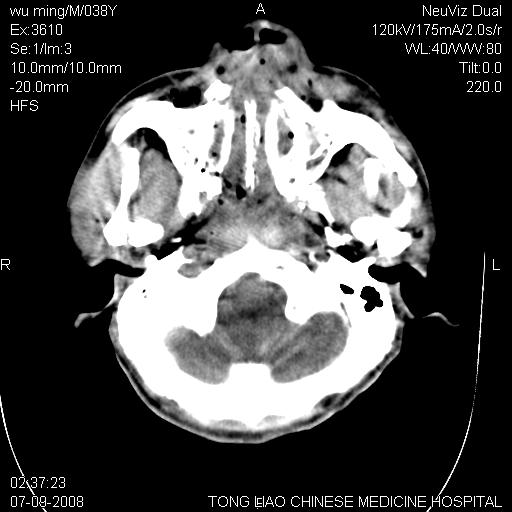

标题: CT14544:患者5楼坠下15分钟后CT扫描,2小时后死亡,请战友指 [打印本页]

标题: CT14544:患者5楼坠下15分钟后CT扫描,2小时后死亡,请战友指

颅底多发骨折。

颅底多发骨折.

考虑:面骨、颅底骨多发骨折,颅内高压(脑肿胀)。

面骨、颅底骨多发骨折,右侧硬膜下小血肿,弥漫轴索损伤,死亡原因可能是多种因素致。

1)颅底骨及颌面骨多发性骨折。2)副鼻窦及双侧鼻腔积血。

颅底骨折,窦腔内积血。考虑死亡原因为脑水肿压迫脑干或因大量失血死亡。

前颅窝颅底骨折,死的原因应该从头部来看不用说就是重度颅脑损伤。

考虑:面骨、颅底骨多发骨折。从五楼摔下还伤着头了,不死才怪;估计有弥漫性轴索损伤。